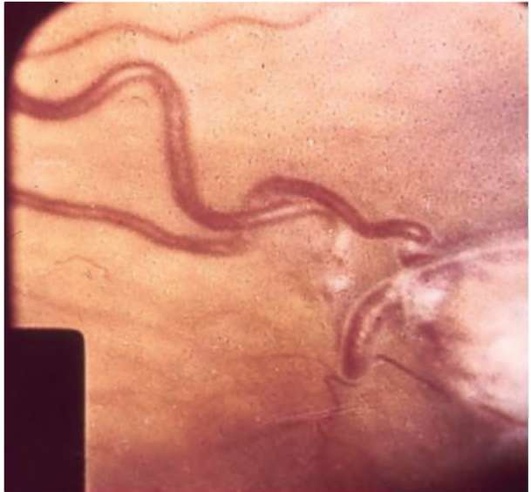

Рис. 20.10. Эмболия центральной артерии сетчатки при пороке сердца